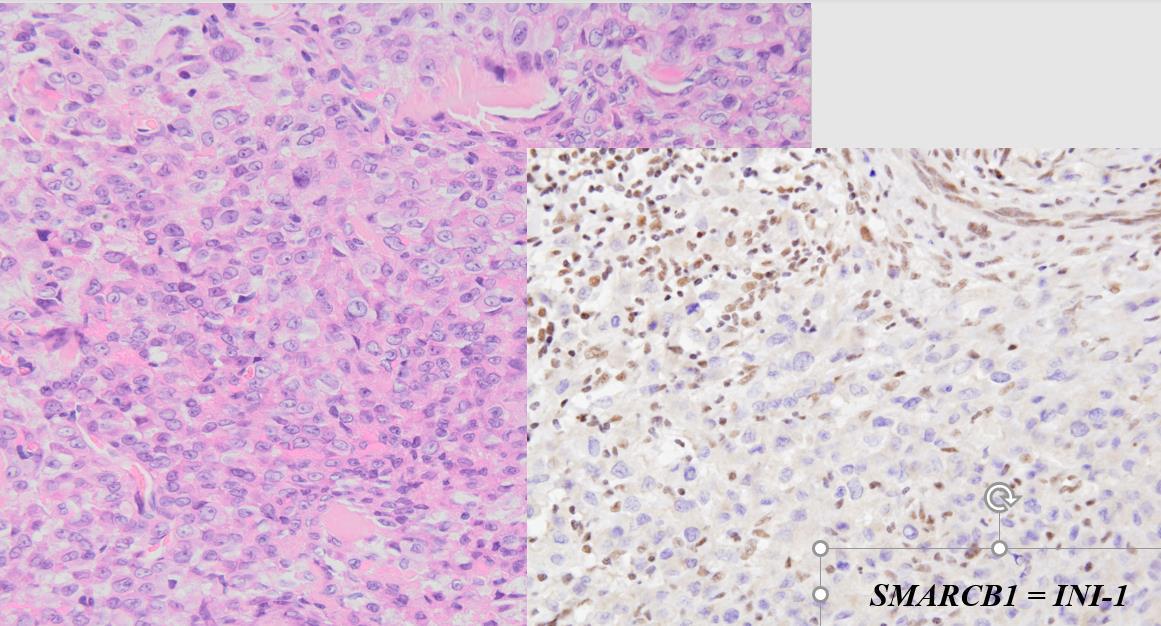

Przedstawione na rycinie utkanie mikroskopowe (rycina strona lewa) i wynik badania immunohistochemicznego na obecność białkowego produktu genu SMARCB1/INI-1 (rycina strona prawa) odpowiadają: